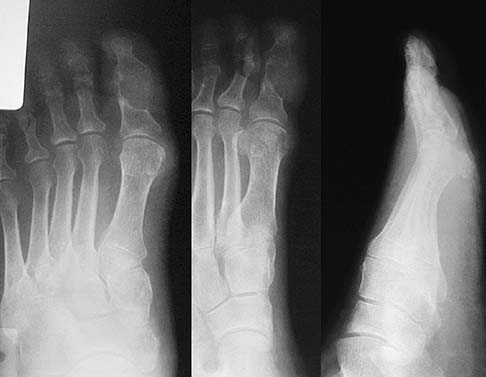

통풍의 정의는 요산이 체내에 축적되어 생기는 병을 의미합니다. 요산은 단백질이 분해되면서 나오는 부산물이라고 생각하면 되는데 이 물질이 일정농도를 유지하면 괜찮지만 그 이상 많이 유지되면 진흙이 쌓이듯이 쌓이게 되는 것이죠. 요즘 들어 헬스 등의 운동문화가 생기게 되어 단백질 관련 음료나 제품을 많이 먹는데, 이런 생활습관도 통풍환자가 많아지는 이유가 될 수 있겠습니다.

이런 결정이 쌓이기 전에 당연히 피속에는 Hyperuricemia 라는 Uric Acid 가 과한 상태가 됩니다. (높아도 정상적으로 지내는 사람들도 많기 때문에 진단에 필수적인 내용은 아니지만, 특이도는 높습니다. 대게 6.7mg/dl 이상일 경우 통풍결절이 생성될 수 있다고 봅니다.)